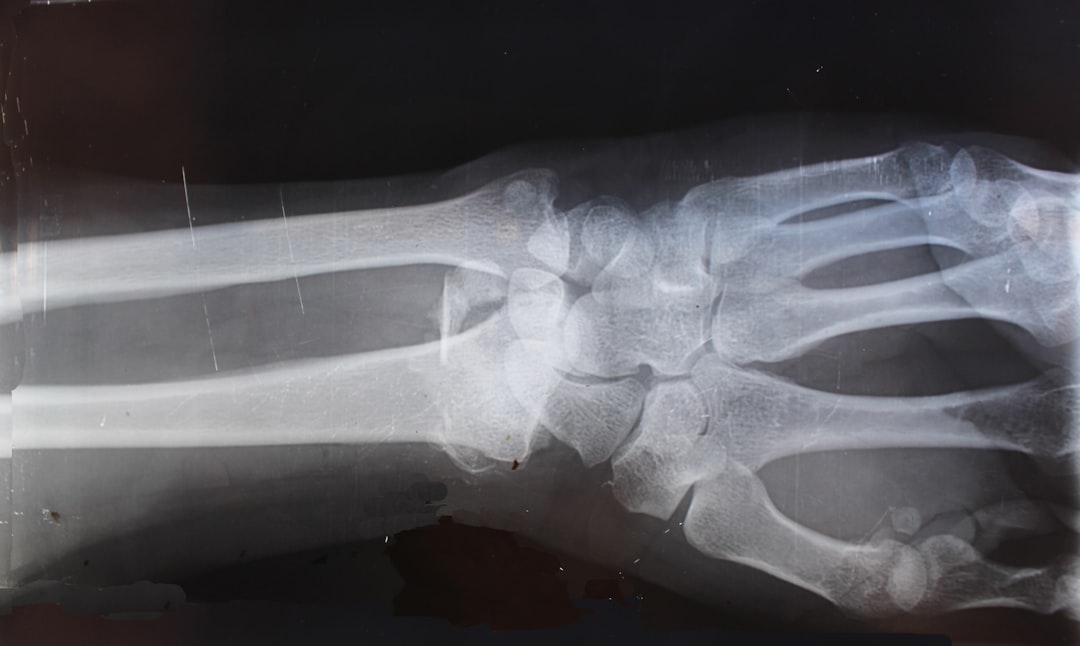

관절염 초기증상은 우리 몸이 보내는 중요한 신호입니다. 관절염 초기증상과 완화 음식의 이해는 조기 진단과 관리에 큰 도움이 됩니다. 초기에는 관절에서 경미한 통증과 뻣뻣함을 느끼기 시작하며, 주로 아침에 더 심하게 나타납니다. 이는 특히 관절이 오랜 시간 동안 움직이지 않을 때 나타나는 현상입니다. 이러한 증상들은 종종 일상적인 피로감으로 오해될 수 있어, 가벼운 경과로 간과하기 쉬운 점이죠.

또 다른 증상으로는 관절 주변이 붓고, 열감이 나는 것입니다. 이럴 경우 관절염 초기증상과 완화 음식을 이용한 관리가 필요합니다. 발이나 무릎 같은 큰 관절에서 시작되며, 점차적으로 다른 부위로도 퍼질 수 있습니다. 통증이 심해지면 운동이나 일상의 활동이 힘들어질 수 있어, 주의가 필요합니다.